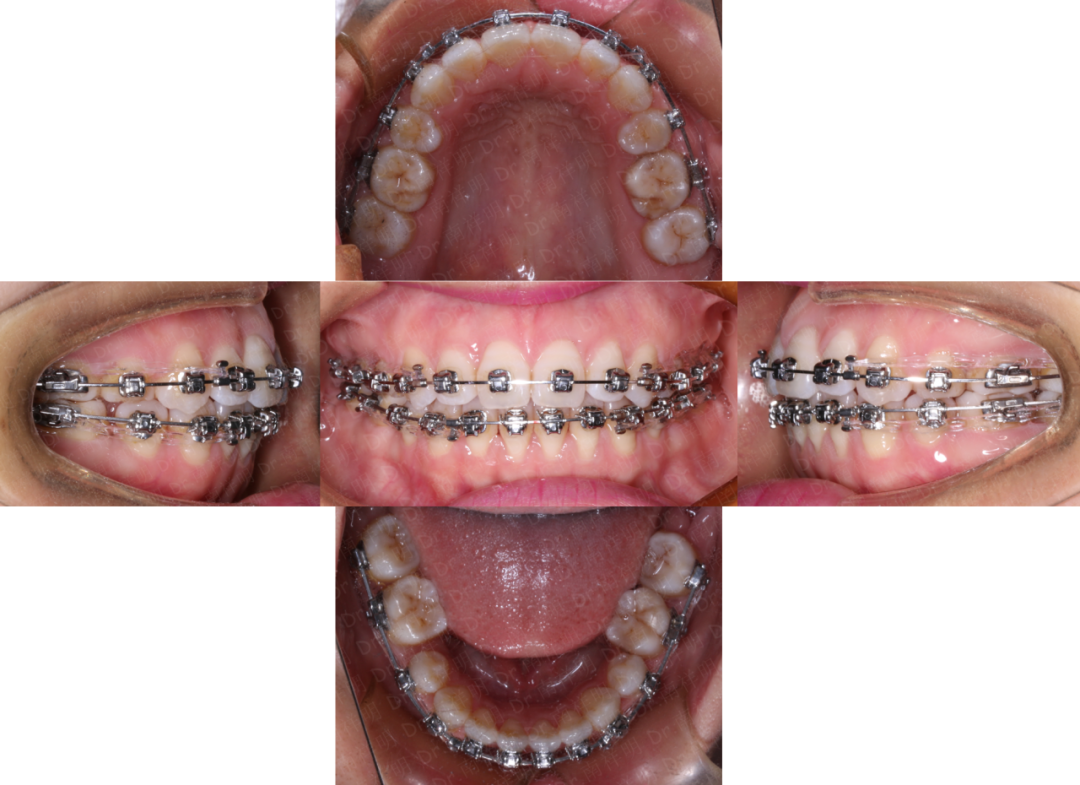

矫治第三个月开始:

上颌16.17;26.27之间颊侧植入支抗钉

在16.17.26.27颊面管中放置0.019*0.025SS片段弓

支抗钉辅助橡皮链弹性牵引压低上颌后牙,进行主动垂直向控制

唇舌肌肉训练继续

下前牙继续排齐第6个月:

上颌后牙压低三个月后,

可见上下前牙区开合明显减小。

此时粘接上颌矫治器,常规排齐

术中拔除了38、48

上下颌0.019*0.025SS

滑动法继续关闭拔牙间隙

同时调整尖牙、磨牙关系

此时正面放松状态下照片可见,上下嘴唇闭可闭合,但是肌肉稍显紧张

上下拔牙间隙关闭完成

上下0.018SS 精细调整,弹性连扎紧密牙列